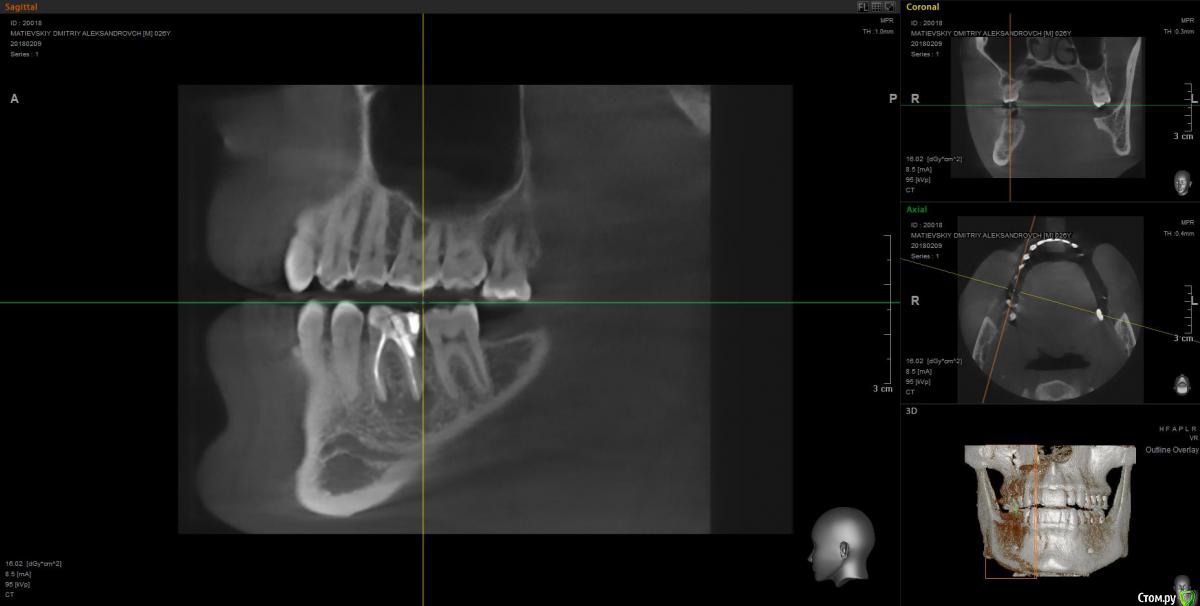

Dmitry91 Опубликовано 13 февраля, 2018 Поделиться Опубликовано 13 февраля, 2018 Добрый день, уважаемые доктора и знатоки! Прошу вашей помощи или мнения по ситуации. Есть проблемный 6й зуб на правой нижней челюсти с огромной пломбой на штифте.Внизу у корней круглые образования (кисты). Под пломбой, похоже, кариес. Стоит ли удалять зуби ставить имплант? Или есть возможность сохранить зуб? Что посоветуете? Если имплант, то какой лучше? Второй вопрос. Нужно ли удалять верхние зубы мудрости (нижних нет)? Похоже рядом с ними на 7ках естьконтактный кариес из-за того, что между зубами мудрости и 7ками застревает пища. Приложил скрины КТ и само 3D КТ в архиве, ссылка ниже. https://yadi.sk/d/kfX43ds43SMxCo Если нужно посмотреть фото с другой стороны, могу сделать. Кто поможет, заранее спасибо!) Ссылка на комментарий

Irouil Опубликовано 13 февраля, 2018 Поделиться Опубликовано 13 февраля, 2018 Удалять восьмерку (вижу только одну) - ОБЯЗАТЕЛЬНО! Удалять шестёрку? Я перспективы лечения не вижу. Какой имплант ставить? Самый надёжный, без оглядки на эстетику. Ссылка на комментарий

колесников Опубликовано 14 февраля, 2018 Поделиться Опубликовано 14 февраля, 2018 6ка удаляется. Желательно одномоментно поставить Имплант. Рекомендую Astra tech. Из дополнительных манипуляций будут:формирователь,0,5г костного материала, пластика десны. Верхняя восьмерка ,с этой стороны , так же удаляется. Ссылка на комментарий